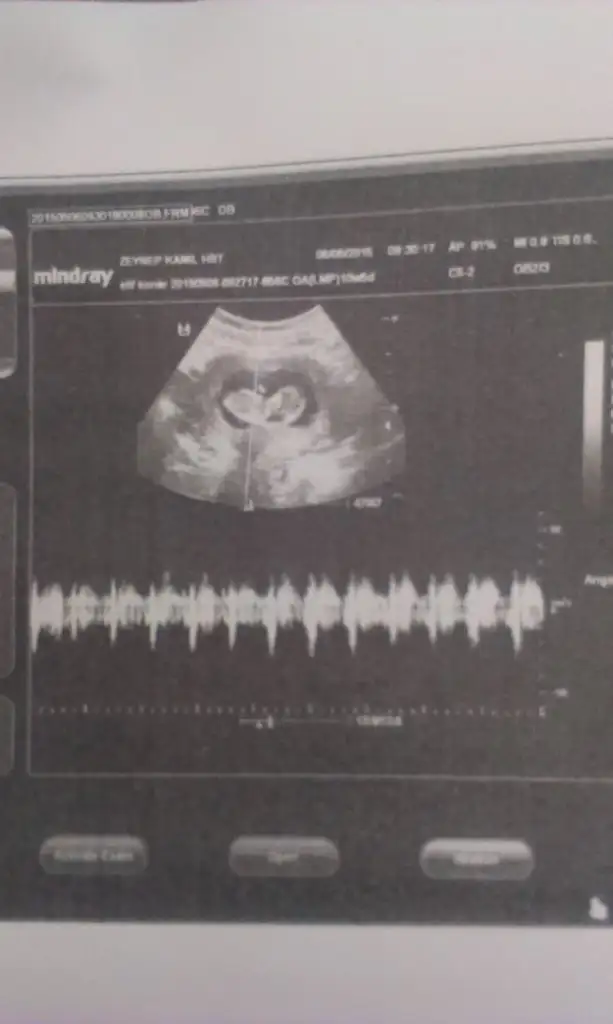

Mrb güzel anneler ve hamisler bizede tahminde bulunur musunuz ? 11+4 gunluguz...

13,9 KB · Görüntüleme: 121

12,6 KB · Görüntüleme: 126